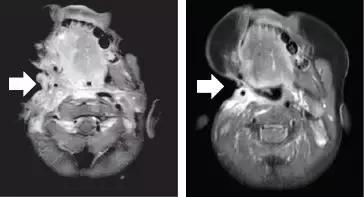

2016年,13岁的的Briana Ayala,被发现在她的腹部有一个罕见的肿瘤,包裹在她的主动脉周围。Briana参加了larotrectinib的1期临床试验,几周之内,她的腹部疼痛和肿胀消失,扫描显示她的肿瘤显着缩小。将近两年后,Briana重返学校!

德克萨斯大学西南分校的研究人员表示,larotrectinib在1期临床试验中93%的儿科患者有效。(照片由比尔布兰森/国家癌症研究所提供)